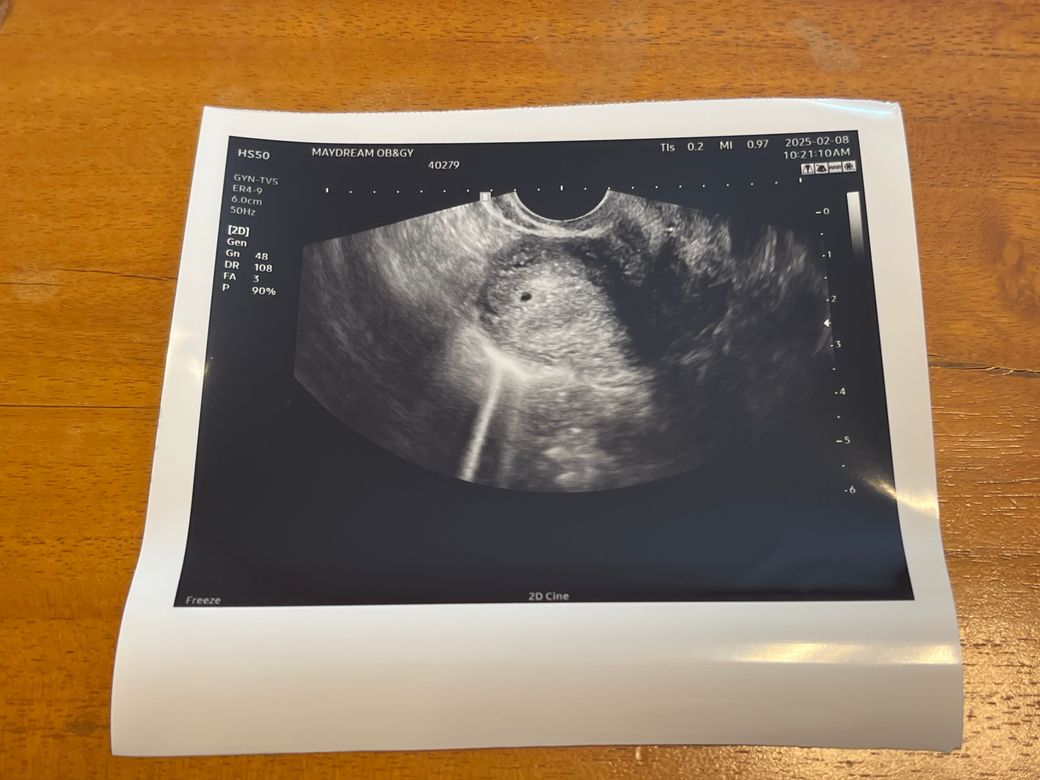

초음파 아기집 크기작은데 괜찮은가요?

주수로는 5주차인데 의사가 아기크기가 3주차크기로

작다고 했어요 0.97이라는데 괜찮게 잘크고 있는걸까요??

자궁외임신 유산 가능성은 없는거겠죠? 출혈은 아직까지

한번도 없었습니다.

• 1번 째 사진

아기집이 정상적으로 자궁내 확인되었다면 자궁외임신 가능성은 배제 할 수 있겠으나 지속적인 초음파 검사를 통해 정상적으로 아기집이 커지는지 확인이 필요하겠습니다.